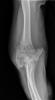

Fractura impactada de húmero .

Fractura compleja de húmero.